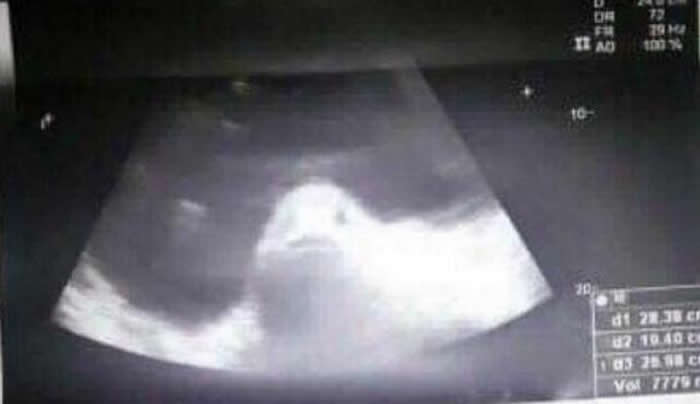

(神秘的地球uux.cn报道)据ETtoday:菲律宾17岁少女贝希娜(Kimberly Robles Besinal)自去(2017)年6月开始,肚子突然不断隆起,家人带她到医院检查,却被超音波照片出现一条「鱼」而直接吓坏。她家人因此相信当地的一个古老传说,如果女生在月经来潮时没穿内裤到海里游泳,就会被鱼怪入侵,进而怀上「鱼脸异形」。

据《太阳报》报导,贝希娜住在菲律宾的一个偏远岛屿,去年6月突然出现胃痛症状,且肚子如同吹气球般不断变大,家人怀疑她跟男生偷尝禁果,马上把她带到医院做检查。结果医生一照超音波把大家全都吓到了,因为萤幕显示,贝希娜的子宫内有一张活生生的鱼脸,而且还看着镜头露出诡异笑容。贝希娜的家人马上联想到当地传说,认为她是被鱼怪给交媾了,进而怀上「鱼脸异形」。